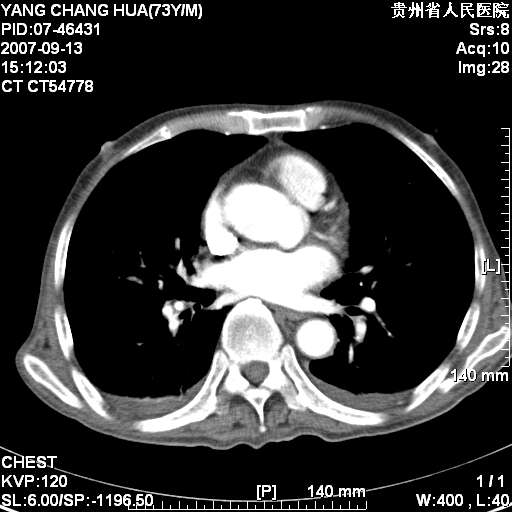

标题: CT9726:M73Y,患者因吞咽困难及腹痛半月入院!全身浅表淋巴结 [打印本页]

图像没有传全。肺部为感染性病灶;肺囊肿;双侧胸腔积液;肝脾肿大;腹水。

双肺部为感染性病灶.双侧胸腔积液;肝脾肿大;腹水.

双肺部为感染性病灶.双侧胸腔积液;肝脾肿大;脾脏密度不均,不除外脾侵润?腹水.

双肺点片状影,以双上肺改变明显.双侧胸腔积液.为感染性病灶,但不除外结核.

肝脾都大..

双肺散在斑片状及多发小结节状阴影,边缘模糊,双上肺野明显,双侧胸膜腔少量积液,纵隔及肺门区未见明显肿大淋巴结,肝脾肿大,脾内见多发低密度区,结合临床考虑恶性淋巴瘤(肺内表现为肺炎肺泡型),单看影像表现,肺结核不能排除。建议结合实验室检查或表浅淋巴结活检。